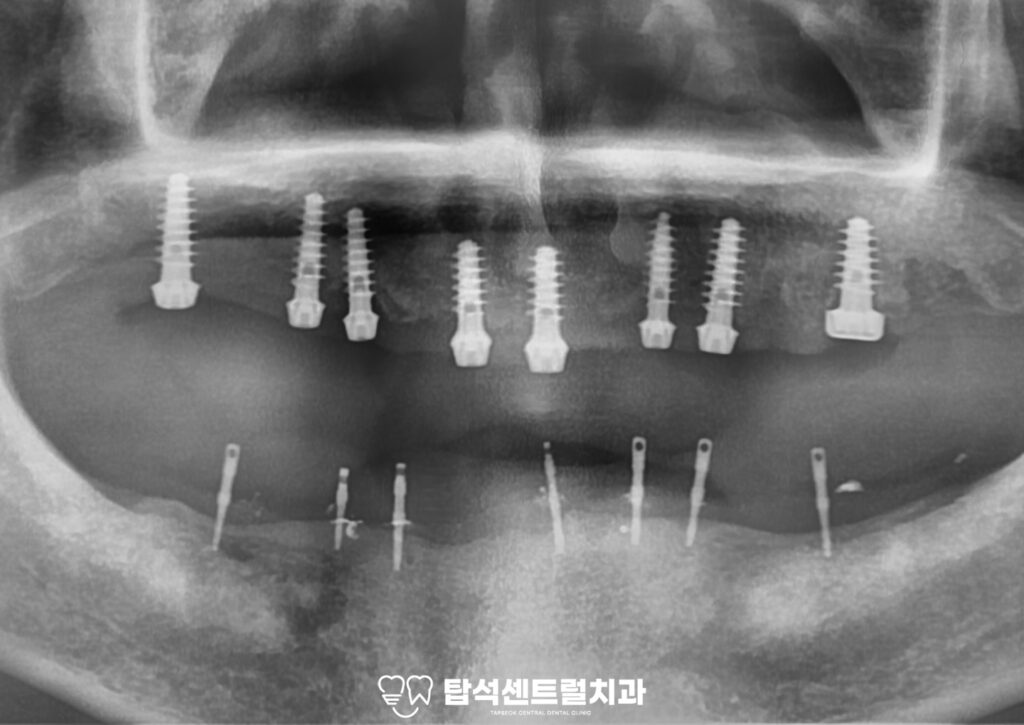

flapless 방식을 통해 잇몸을 절개하지 않고

픽스처를 심어볼 수 있습니다.

flapless 방식은 잇몸을 절개하지 않는 방식으로,

수술 후의 부종과 출혈을 최소화하며

회복 기간도 현저히 줄어듭니다.

더불어 절개를 하지 않기 때문에

환자가 느끼는 통증 또한 줄어듭니다.

임플란트 식립 후에는 골유착이 이루어질 때까지

일정 기간 회복하는 기간을 거칩니다.